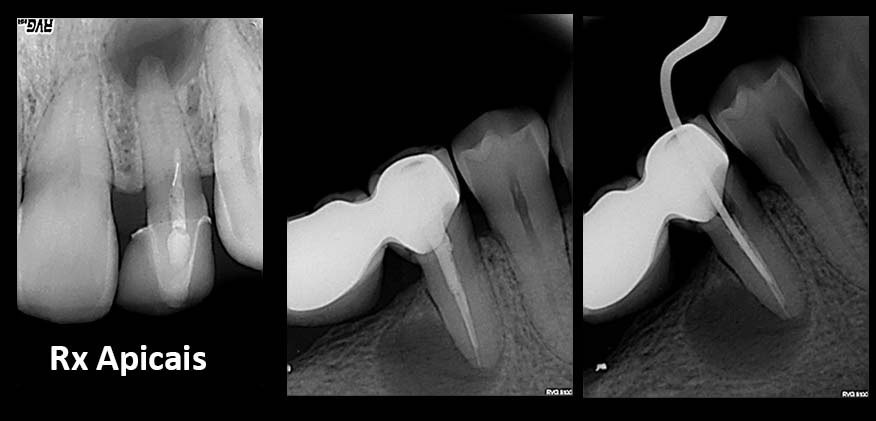

2. Radiografias

Tratamentos urgentes serão executados se necessário, como no caso à esquerda.

SOS